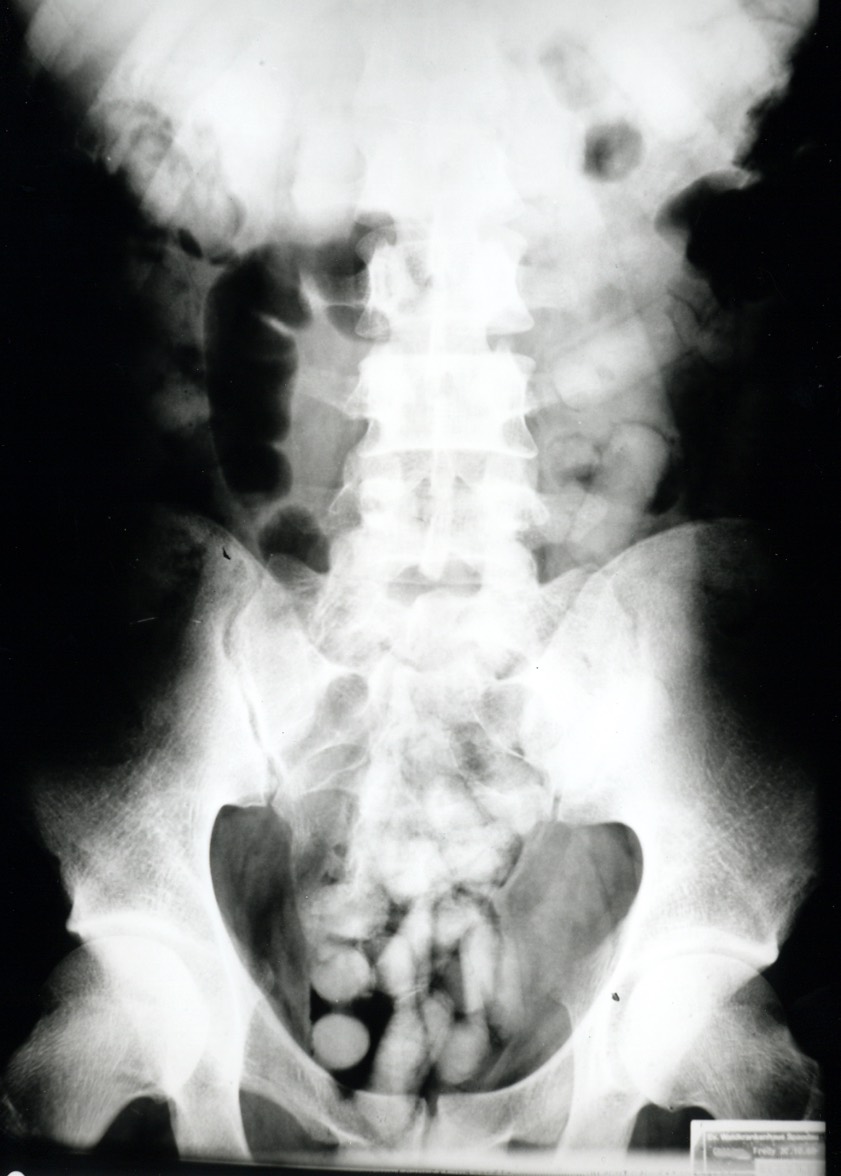

"Bei der Zoll-Kontrolle verstrickte sich der Mann in Widersprüche, was seine Auskünfte über Reisezweck und -dauer anging", wurde heute erklärt. "Die Beamten führten daraufhin einen Drogen-Wischtest durch, der das Kokain anzeigte." Da weder am Körper noch im Handgepäck des Kolumbianers allerdings Kokain gefunden worden sei, habe der Mann im Krankenhaus geröntgt werden müssen. "Das Röntgenbild zeigte Fremdkörper und bestätigte damit den Verdacht der Zöllner", berichtet Marie Müller, die Presse-Sprecherin des Hauptzollamts München.

Als Bodypacking wird das Verschlucken von Betäubungsmitteln zum Zweck des Transports bezeichnet. Die Drogen werden dabei in speichel- und magensäure-resistente Beutel wie zum Beispiel Kondome verpackt. "Platzt nur eines dieser Behältnisse im Magen, bedeutet das in den meisten Fällen den sicheren Tod", betont der Zoll.